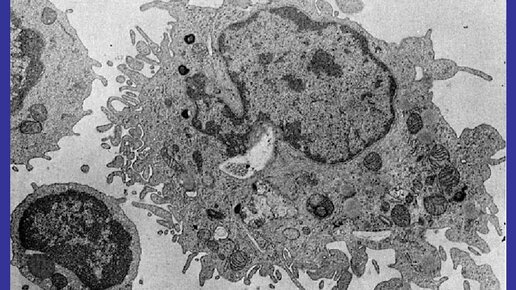

Ретикулоэндотелиоциты - клетки, способные фагоцитировать инородные частицы и накапливать в цитоплазме коллоидные вещества. К ним относятся макрофаги рыхлой соединительной ткани, ретикулярные клетки кроветворных органов, эндотелиальные клетки капилляров кроветворных органов т.д. Ретикулоэндотелиальная система, иными словами, система, представленная клетками - защитниками, то есть общую совокупность моноцитов, мобильных макрофагов, фиксированных тканевых макрофагов, некоторых специализированных эндотелиальных клеток костного мозга, селезенки, лимфатических узлов...